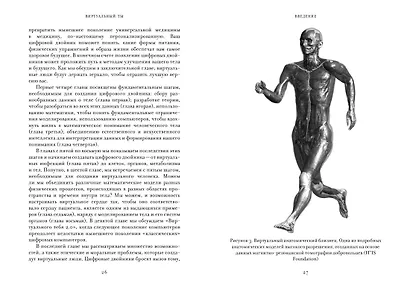

Только представьте: вместо утомительного осмотра врача и рецепта на лекарство с недоказанным действием – мгновенный список рекомендаций, рассчитанных именно на ваш организм и обладающих 100-процентной эффективностью. Невозможно, скажете вы?

Вовсе нет – уверены Питер Ковени и Роджер Хайфилд. Новейшие исследования в области создания цифровых близнецов, о которых они рассказывают в этой книге, помогут предсказать риски появления заболевания, эффективнее испытывать лекарства, выбирать оптимальный режим дня и питания, а также определить методы лечения для улучшения здоровья и продления жизни человека. Осталось лишь решить несколько проблем технологического и этического порядка, чтобы «виртуальный вы» стали реальностью.